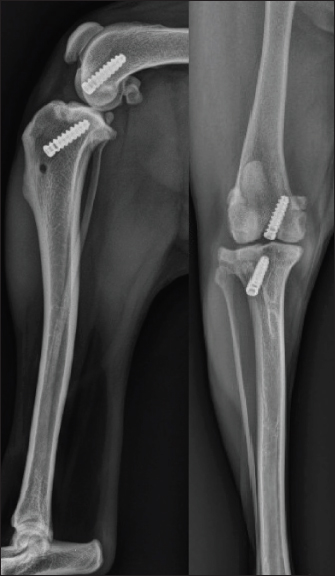

The dog was anesthetized with tiletamine (0.5 mg/kg)/zolazepam (0.5 mg/kg) + medetomidine (0.01 mg/kg) + morphine hydrochloride (0.5 mg/kg) by induction. An isoflurane relay (between 0.8 and 1%) in half-closed circuit was carried out at a flow rate of 1 l/minute. A constant rate infusion (2 ml/kg/hour) of a mixture of 250 ml of physiological serum + 30 mg of morphine + 202.75 mg of lidocaine + 75 mg of ketamine was administered. A single injection of cephalexin at 30 mg/kg was given at the start of the surgical preparation. The dog was placed in dorsal recumbency and prepared for aseptic surgery on the right hindlimb using chlorhexidine. A joint distractor supported by two 2.5-mm pins was placed on the stifle. The arthroscopic port was placed on the lateral side through a 5-mm lateral parapatellar incision performed with an 11-mm blade. Arthroscopic evaluation of the joint revealed inflammation of the medial meniscus without structural damage (Fig. 2A) and confirmed the complete rupture of the CdCL in its distal part at the tibial insertion (Fig. 2B). The lateral meniscus and the cranial cruciate ligament were intact. The lateral parapatellar incision was made 3 cm wider to allow the complete resection of the damaged CdCL with an 11-mm blade under arthroscopic control. The bone tunnels for femoral and tibial fixation of the synthetic ligament were drilled under arthroscopic control. A 2-mm guide wire was inserted at the femoral footprint of the origin of the CdCL in a caudo-medial direction to exit on the medial side of the femoral condyle under arthroscopic guidance. The femoral tunnel was drilled over the guide wire using a 3.6-mm cannulated drill bit (Fig. 3A). The tibial tunnel was created with the help of a tibial drilling guide. A stab incision was made at the caudal aspect of the joint to insert the tip of the tibial drilling guide, which was positioned at the footprint of the proximal tibial insertion of the CdCL under arthroscopic control, and oriented in a distal and cranio-lateral direction. A stab incision was made on the proximal aspect of the craniolateral aspect of the tibia to position the sleeve of the drilling guide. The appropriate position of the tip of the tibial drilling guide was assessed arthroscopically before drilling. The same technique as that used for the femoral tunnel was used to drill the tibial tunnel (Fig. 3B). The UHMWPE implant (Novalig 4000, Novetech Surgery, Monaco) was passed through the tibial and femoral tunnels using a passing tube and a wire loop (Fig. 4A). A 4.5 × 20-mm interference screw was placed from inside-out (Fig. 4B) (Rafael et al., 2020). The UHMWPE implant was then passed through a 3-mm-wide sliding tunnel, drilled perpendicularly through the tibial crest using a medial approach and located near the distal exit of the tibial tunnel. This setup increased the precision of the tensioning of the prosthesis using the created counter-support and facilitated the placement of the interference screw. Once satisfactory tension was obtained, the implant was locked with a second 4.5 × 20-mm interference screw placed from outside-in (Fig. 4C) (Rafael et al., 2020). Once the implant was securely locked, no residual drawer sign was observed and a normal range of motion was reported.

Fig. 2. (A) Arthroscopic view of inflammation of medial meniscus without structural damage. (B) Arthroscopic view of ruptured CdCL.